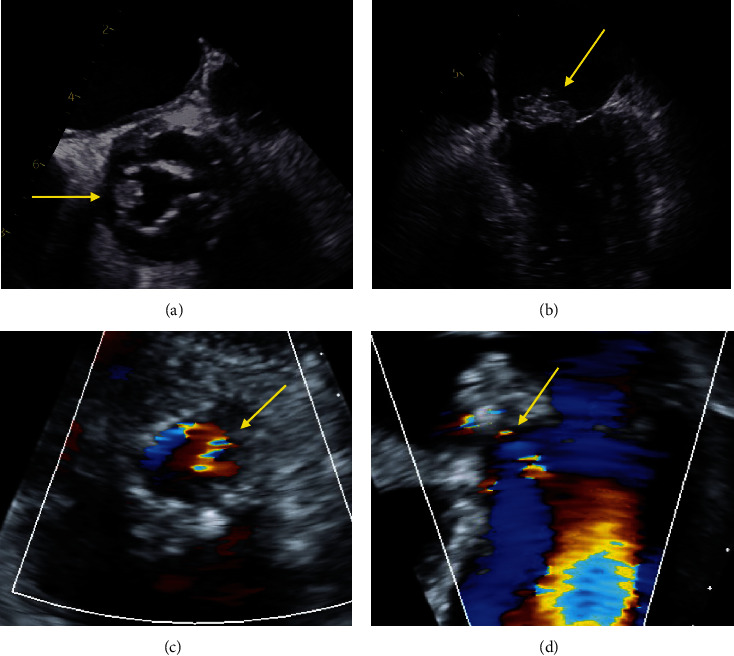

主动脉心房瘘是感染性心内膜炎的一种罕见并危及生命的并发症,通常通过观察主动脉和心房之间的连接并伴有连续血流来诊断。一名患者患有生物人工瓣膜和原生瓣膜肠球菌性心内膜炎,并伴有多种并发症,其中包括经食道超声心动图彩色 M 型诊断出的主动脉心房瘘。我们回顾了主动脉心房瘘的特征,并利用这个病例展示了如何利用 M 模式在诊断不确定的情况下提供更好的时间分辨率。

Aorto-atrial fistula is a rare and life-threatening complication of infective endocarditis, classically diagnosed by visualizing a connection between the aorta and atrium with associated continuous flow. A patient presented with bioprosthetic and native valve enterococcal endocarditis with multiple complications, including an aorto-atrial fistula that was diagnosed by color M-mode on transesophageal echocardiography. We review the features of aorto-atrial fistula and utilize this case to demonstrate how M-mode can be leveraged to provide improved temporal resolution in the setting of diagnostic uncertainty.